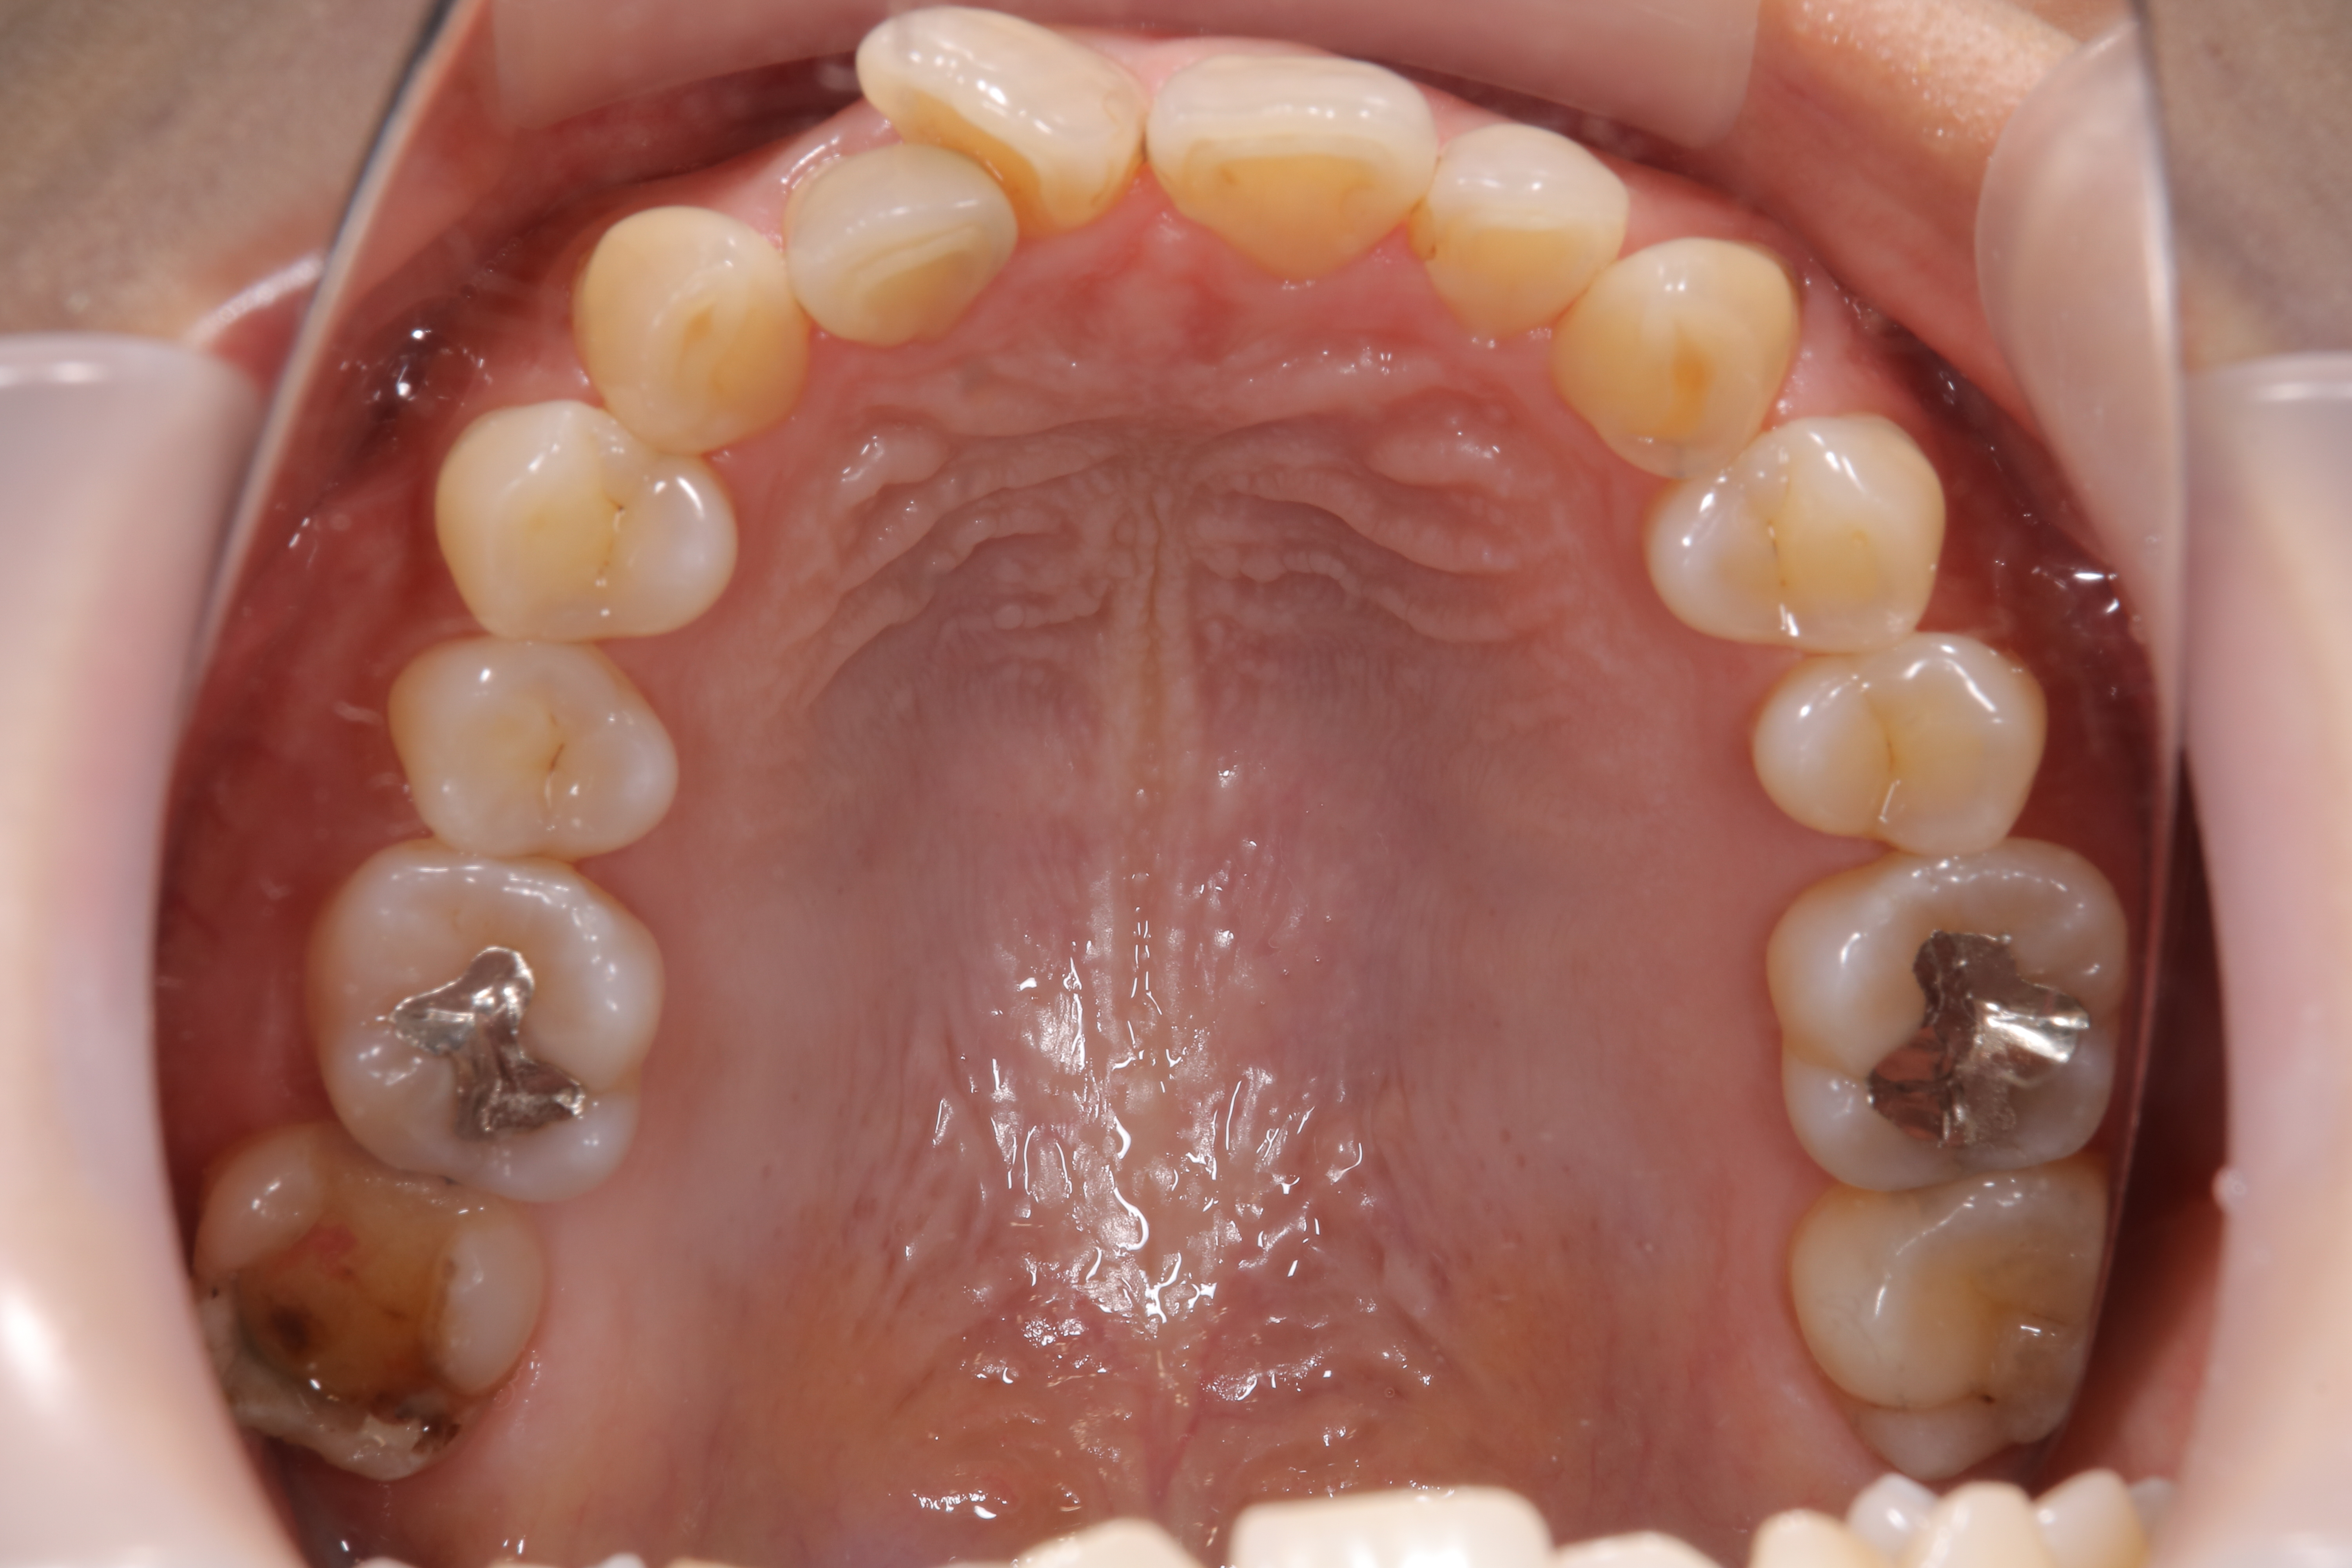

審美歯科治療

症例紹介